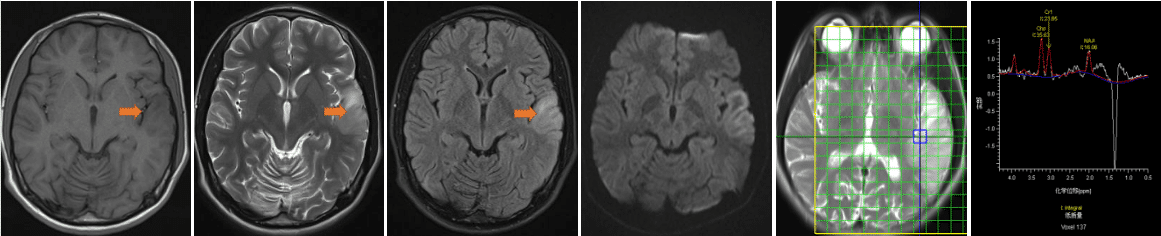

一、病例特点:患者中年男性,急性发病;临床表现为意识水平下降伴认知减退、情感异常、吞咽障碍及二便失禁;既往曾行股骨头置换术,留有左下肢活动欠灵活;吸烟史30年,平均约20支/日,已戒烟1周;饮酒史30年,平均约半斤/日,已戒1周。专科查体:意识模糊,言语稍笨拙,双双眼左视时可见水平粗大眼震,双眼外展均受限,右侧肢体肌力Ⅲ+级,右侧巴氏征阳性,脑膜刺激征阴性,余查体不配合。辅助检查: 肝肾功能+电解质 :总蛋白:63.9g/L,↓;白蛋白(溴甲酚绿法):30.1g/L,↓; 白球比:0.9,↓; 丙氨酸氨基转移酶:113U/L,↑;天冬氨酸氨基转移酶:178U/L,↑;钠:133mmol/L,↓; 氯:98.0mmol/L,↓; 镁:0.74mmol/L,↓; 血常规 :白细胞计数:3.39×10^9/L,↓;红细胞计数:2.81×10^12/L,↓; 血红蛋白量:110g/L,↓; 红细胞比积:0.310,↓;平均红细胞体积:111.4fL,↑; 平均红细胞血红蛋白量:39.10pg,↑; 红细胞分布宽度SD:56.7fL,↑;血小板计数:93×10^9/L,↓维生素B12:>1476pmol/L,↑; 叶酸:5.07nmol/L,↓; 贫血六项:铁蛋白:>2000μg/L,↑;转铁蛋白:1.97g/L,↓; 血清总铁结合力:42.40μmol/L,↓; 铁:8.8μmol/L,↓。二、神经影像头MR(2024-3-17) :双侧丘脑及双侧额叶皮层见多发对称性长T1长T2信号,FLAIR像为高信号,DWI上病变呈高信号影,ADC上病变呈等信号影。 影像结果:双侧丘脑及双侧额叶皮层对称性异常信号,建议进一步检查。 头MRS(2024-3-26):2.02ppmNAA 峰正常(NAA/Cr<1),3.20ppm胆碱峰(Cho)轻度上升(Cho/Cr>1),2.4ppm谷氨酸复合物峰(β,γ-Glx)、3.05ppm肌酸峰(Cr)、3.90ppmCr的第二峰均可明显分辨,未见明显异常。综合表现为:Cho/Cr上升。MRS示双侧丘脑病变区Cho/Cr轻度上升,请结合临床。三、临床诊断:Wernick 脑病Tips 心情驿站